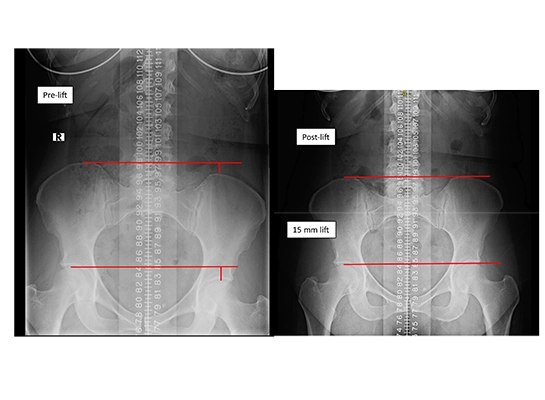

This condition compromises the integrity of your entire kinetic chain, making long-term stability impossible. At Limitless Chiropractic, we treat LLI as a critical structural disorder. We utilize advanced, weight-bearing X-ray analysis and precision measurement, the gold standard in LLI diagnosis—to quantify the exact discrepancy and guide a corrective, long-term solution.

To correctly manage LLI, accurate measurement is non-negotiable. Our method goes beyond tape measure approximations; we use specialized X-ray analysis to differentiate between an anatomical short leg (a true bone length difference) and a functional short leg (caused by pelvic misalignment). This distinction is vital because a functional short leg requires Corrective Chiropractic Care, while an anatomical short leg requires the precise use of a heel lift.